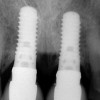

Figure 10  In these adjacent implants placed in the central and lateral positions, note the excellent interproximal bone but minimal interimplant distance.

Figure 10

Figure 11  Soft-tissue levels were acceptable at the time of placement of the final restoration.

Figure 11

Figure 12  At 6 months postinsertion, the papilla receded as bone was lost.

Figure 12

Figure 13  Twelve months after placement, soft tissue migrated apically as bone between the implants continued to resorb.

Figure 13